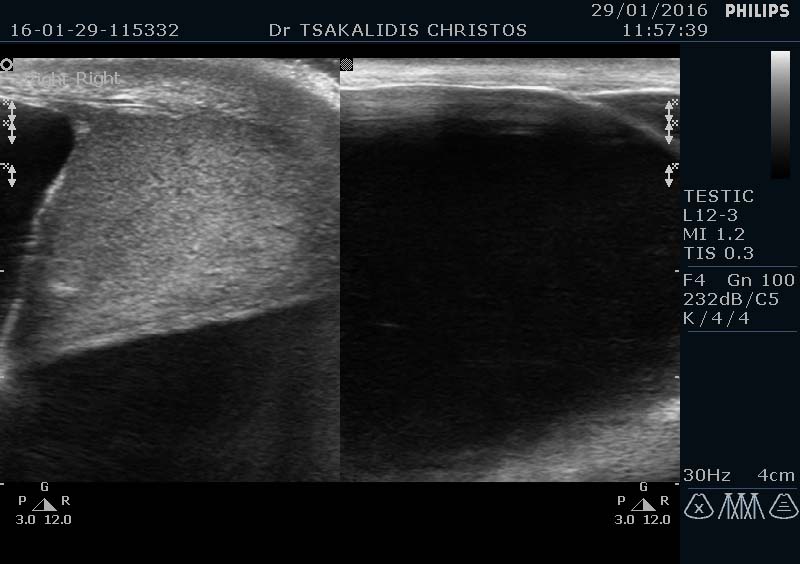

Περίπτωση υδροκήλης ασθενή κ Τσακαλίδη

Υπέρηχος υδροκήλης ασθενή κ Τσακαλίδη